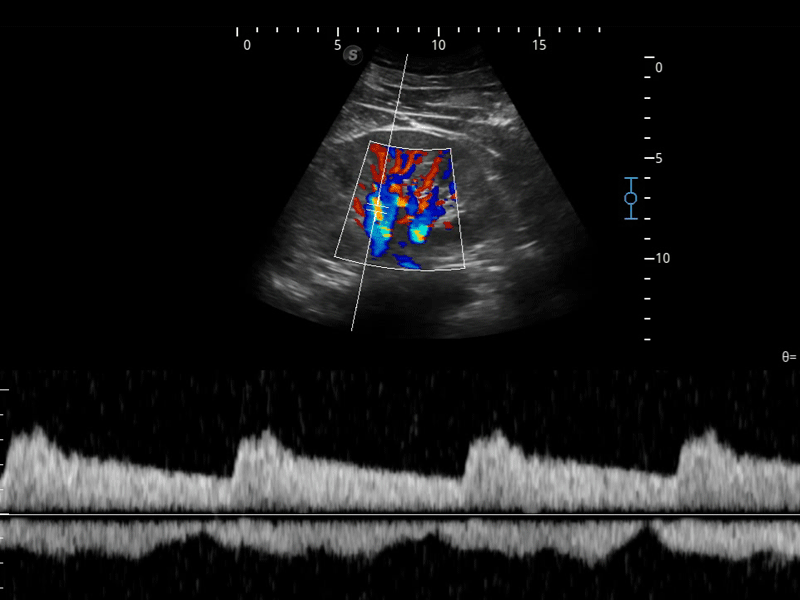

组织多普勒

组织多普勒成像功能,可提供心肌运动速度和其他临床信息,使临床医生能够分析和比较患者心脏不同部位的运动。

造影成像

造影成像功能和定量分析工具包使医生能够更好的评估血流灌注情况。独特的动态声压控技术有效控制造影剂的声压,保证更长的造影剂持续时间,更好的观察病变灌注的延迟相位。

临床图像